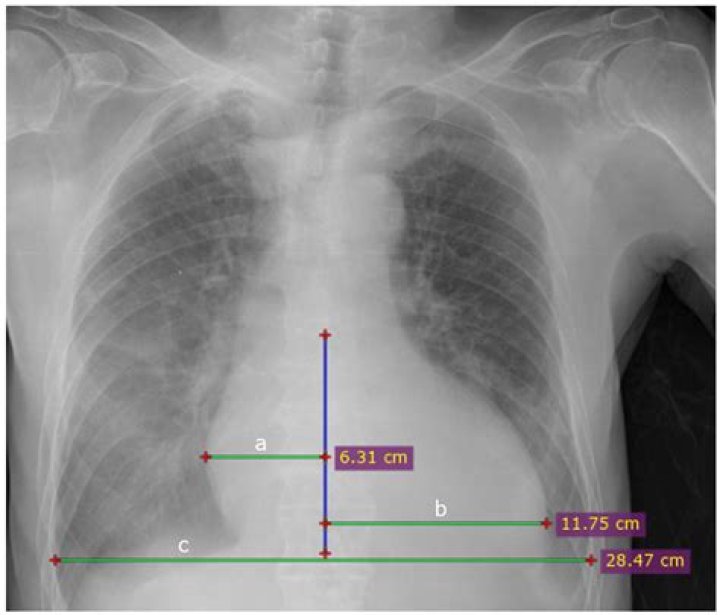

Transverse cardiac diameters of 15.5cm for males and 14.5cm for females are considered as the normal upper limits respectively; An increase in the transverse cardiac diameter by 1.5cm on two consecutive chest radiographs taken at short intervals is considered abnormal, and a sign of cardiomegaly.

Chest x-ray -Cardiothoracic Ratio -CARDIAC SIZE - Cardiomegaly